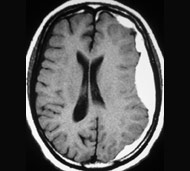

Діагностування гематоми може бути складним. Однак лікарі в основному припускають, що прогресуюча втрата свідомості після травми голови викликається крововиливом в череп, якщо не доведено інше. Кращий спосіб визначити локалізацію і розмір гематоми - це візуалізація.

- комп'ютерна томографія (КТ). Для отримання зрізів КТ застосовується сучасний рентген-апарат, підключений до комп'ютера для виконання детальних зображень головного мозку.

- магнітно-резонансна томографія (MРТ). Зрізи МРТ отримують з використанням великого магніту і радіохвиль, які виробляють комп'ютерні зображення. Під час МРТ пацієнт лежить на рухомому столі, який вводиться в трубу або тунель.

Виконання КТ та МРТ є безболісним обстеженням.